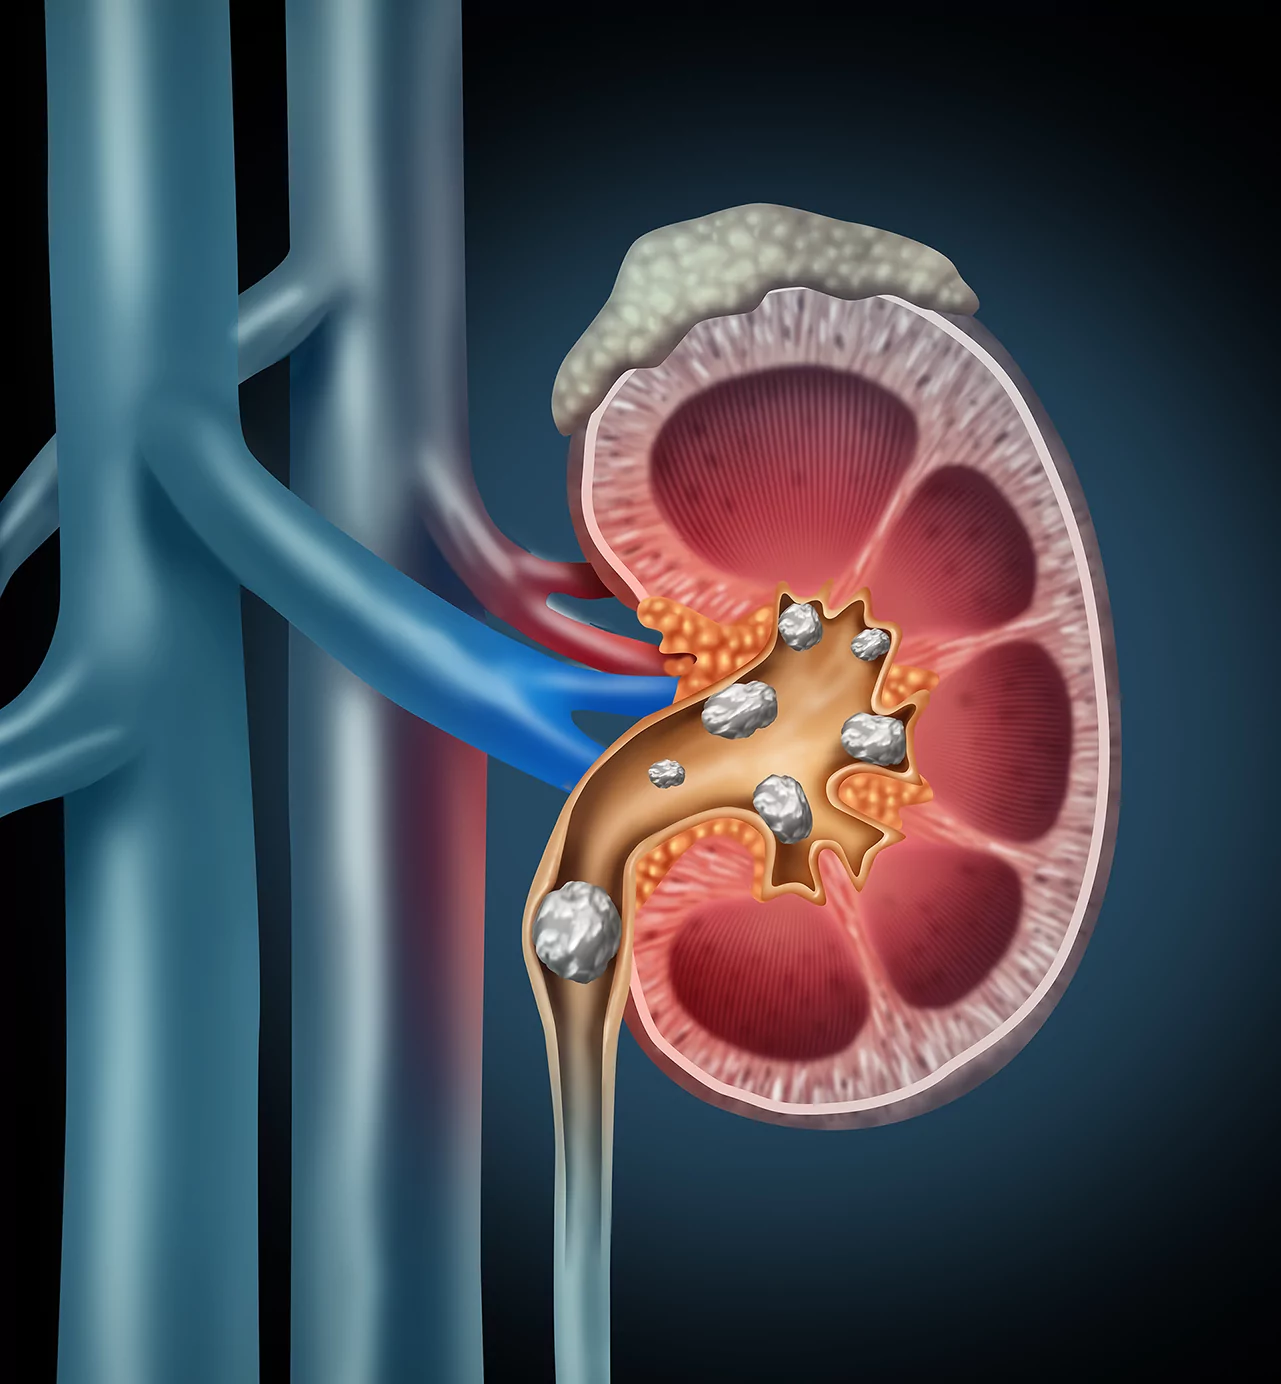

What is RIRS and How Does It Work?

During PCNL Treatment in Raipur:

- A flexible scope is passed through the urethra

- It reaches the kidney without any incision

- Laser is used to break stones into fine particles

- Fragments are either removed or passed naturally

This technique avoids cuts, reduces pain, and ensures quicker recovery.

Technology and Techniques Used in RIRS

Flexible Ureteroscope Technology

Allows easy navigation inside the kidney for accurate treatment.

Laser Stone Fragmentation

High-energy laser breaks stones into fine particles during Laser Stone Surgery in Raipur.

Dusting and Fragment Removal Techniques

Ensures complete stone clearance with minimal discomfort.

Stent Placement When Required

A temporary stent may be placed to ensure smooth urine flow after the procedure.